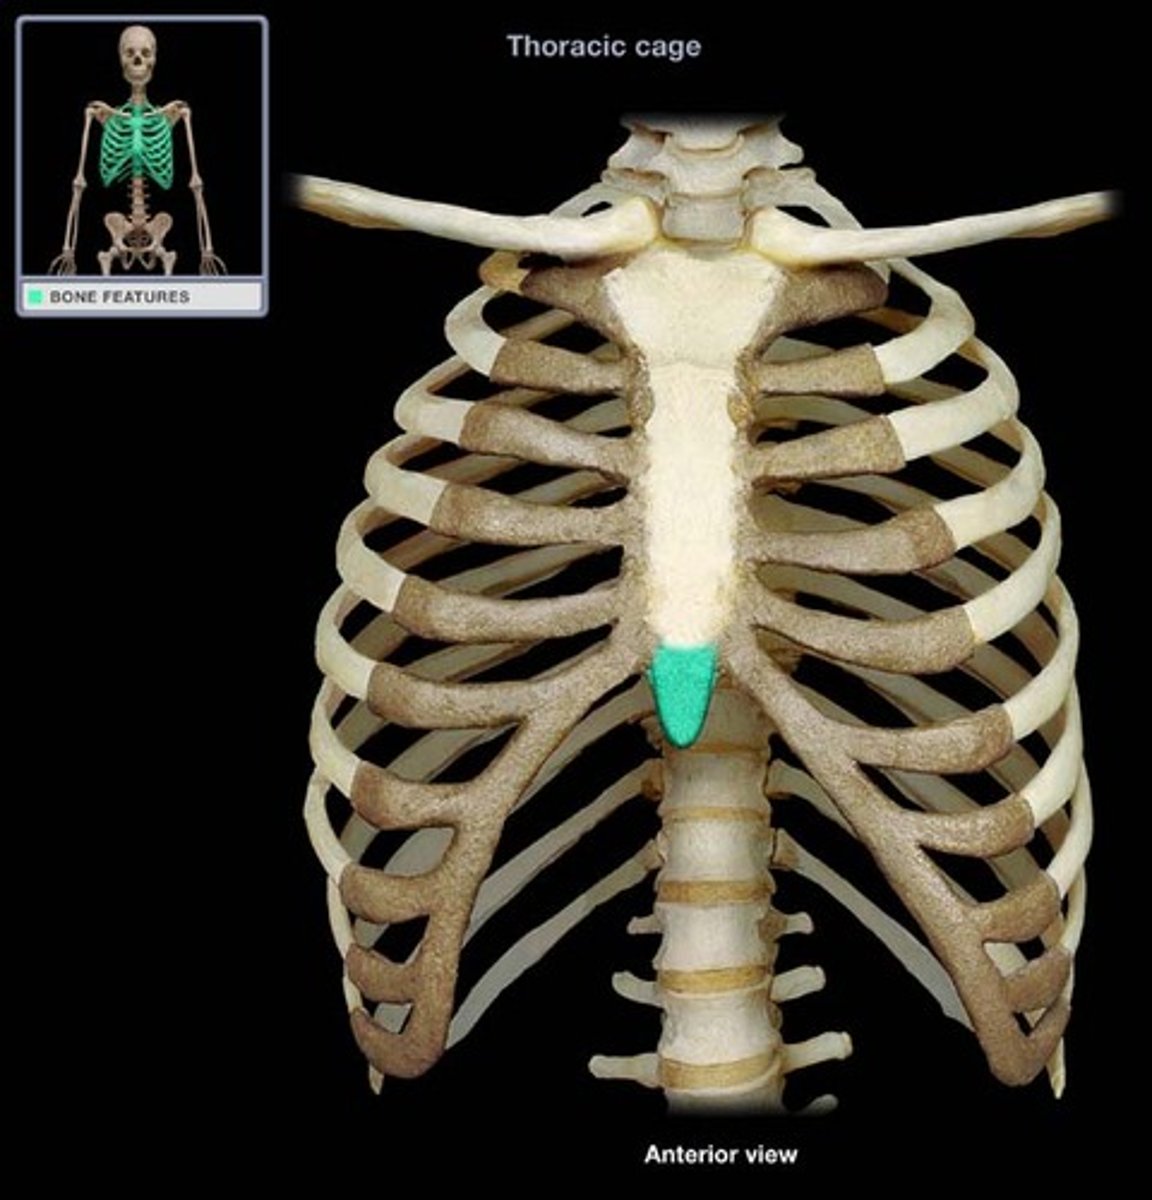

Xiphoid process of sternum

(T10)

Midline marker for superior level of liver, central tendon of diaphram

inferior border border of heart

cartilaginous in young people. Bone after 40.

What is the xiphisternal joint level to?

T9

xiphisternal joint

point where sternal body and xiphoid process fuse, symphysis